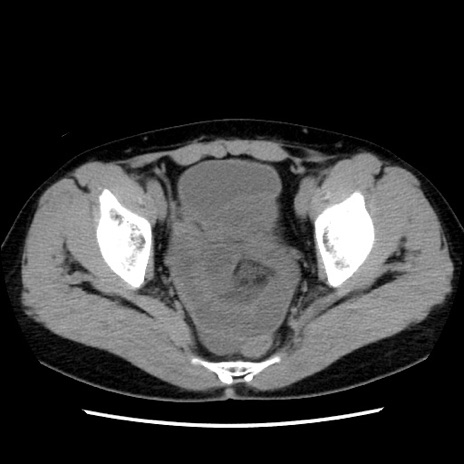

症例10(横断像)

【症例】 50歳代女性

【主訴】 腹痛

【現病歴】前日生レバーを食べた。今朝に排便あり。 昼前に突然発症の腹痛を生じ、当院救急外来を受診した。

【既往歴】 子宮筋腫にてで子宮全摘後

【身体所見】 意識清明、腹部:平坦、軟、下腹部やや左を中心に圧痛・反跳痛あり、筋性防御あり

【データ】WBC 7800、CRP 0.07